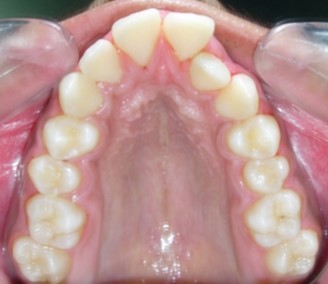

Intraoral assessment. (Figure 1d,Figure 1e,Figure 1f,Figure 1g,Figure 1h).

Figure 1g.Pre-treatment intra-oral-Upper occlusal

The maxillary arch was V-shaped with severely proclined and rotated maxillary incisors with a palatally placed 12. The mandibular arch was U-shaped with severe crowding of mandibular incisors, with 43 partially erupted and buccally placed with transpositioned 42 and 43, with 42 mesiolingually rotated, 33 distolingually rotated and 34 distolingually rotated and buccally placed.

Severe increase in overjet and deep bite were both observed. The maxillary midline coincided with the skeletal midline but the mandibular midline was shifted to the right side by 1 mm. Bilateral maxillary posterior crossbite was also observed. On right side the molar relation was Class I and on the left side it was Class II. The canine relation was Class II on the left side and the curve of Spee was increased.

Figure 10a.Pre aexpansion - maxillary arch